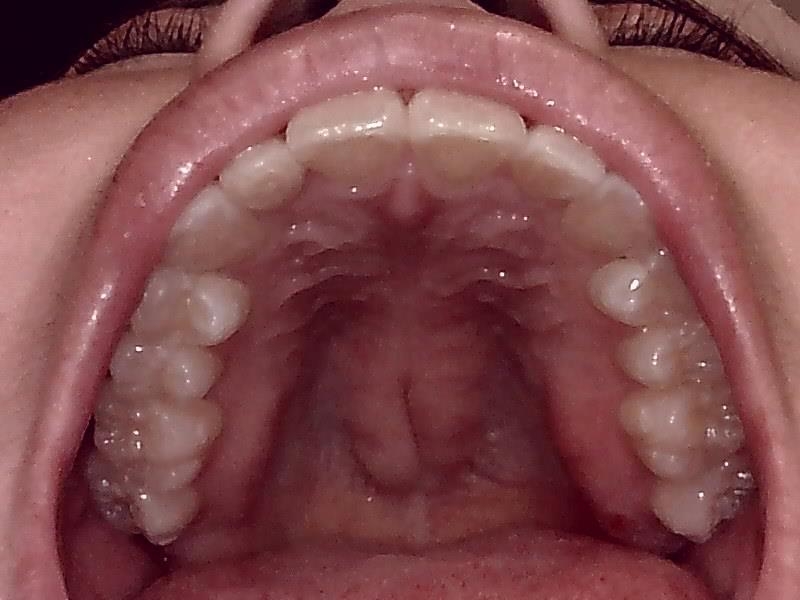

上顎